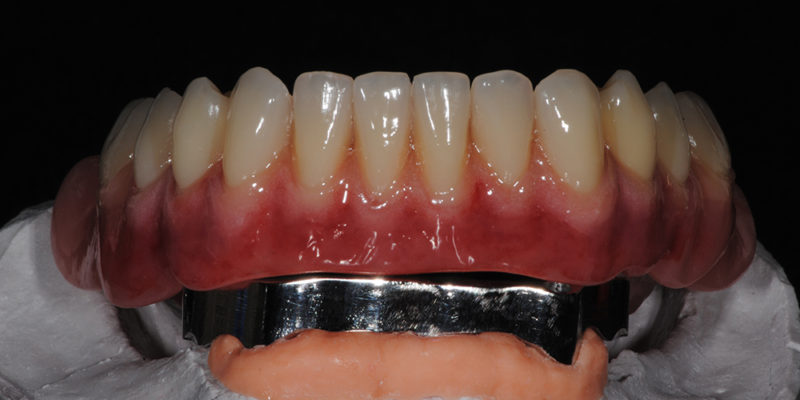

Ripristino dell’arcata superiore ed inferiore su overdenture su barra